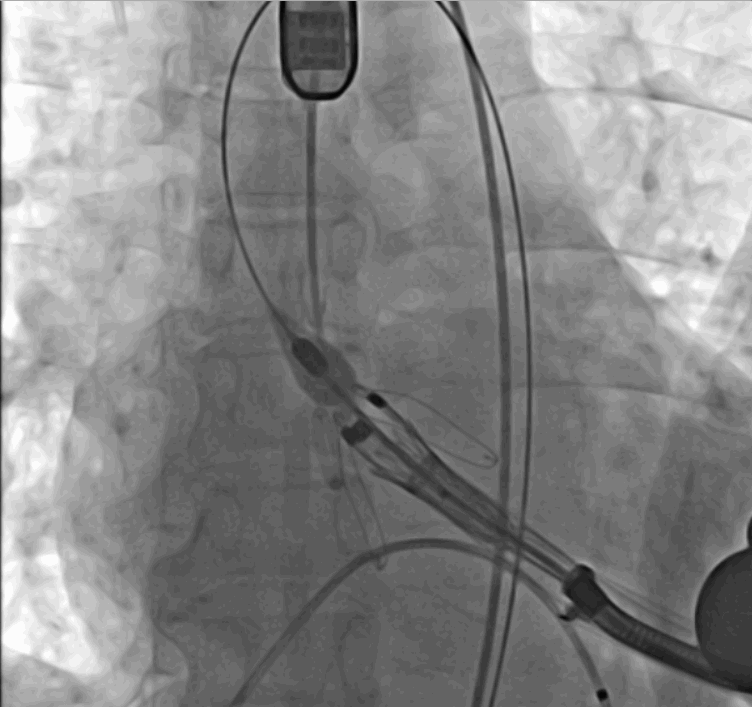

術(shù)中瓣膜釋放過程

手術(shù)采用經(jīng)心尖入路,對患者進(jìn)行全麻后,在左側(cè)心尖處做3-4cm微創(chuàng)手術(shù)切口,在DSA及超聲引導(dǎo)下手術(shù)順利完成。從導(dǎo)入器械到完成瓣膜置入,僅耗時約10分鐘。術(shù)后即刻主動脈瓣返流程度由術(shù)前大量返流轉(zhuǎn)為消失,患者于導(dǎo)管室拔除氣管插管,次日由ICU轉(zhuǎn)入普通病房。